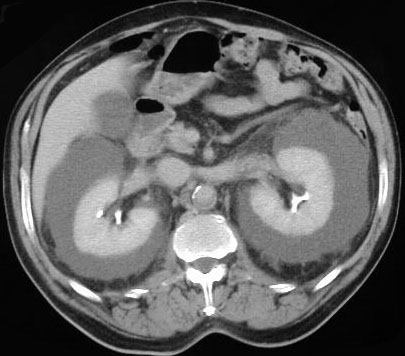

CASO 1: Paciente de 58 años que se realiza TC de abdomen tras historia de dolor abdominal y hematuria microscópica. Refiere pérdida de peso en las últimas semanas.

Estamos ante una afectación bilateral del espacio perirrenal, más evidente en el lado derecho, por masas de densidad de partes blandas en un paciente con numerosas adenopatías retroperitoneales. Estaría indicado realizar una biopsia, ya que el diagnóstico principal orienta hacia un síndrome linfoproliferativo, espcialmente linfoma no Hodgkin tipo B.

2. LINFOMA.

El linfoma renal presenta una gran variedad de manifestaciones. Entre un 3 y un 8 % de linfomas estudiados por TAC tienen afectación renal o perirrenal, más frecuentemente el tipo no Hodgkin.

Patrones de afectación del linfoma renal:

- Multiples masas renales en el riñón (+frecuente)

- Lesión solitaria.

- Adenopatías retroperitoneales con extensión directa a riñón y EPR (nuestro caso de hoy).

- Afectación del espacio perirrenal aislada.

- Infiltración difusa de uno o ambos riñones.

En el caso de que el linfoma afecte al EPR, se ve como una masa homogénea que ocupa este espacio y que desplaza el riñón hacia adelante, ocupando a menudo también el espacio pararrenal anterior. La afectación aislada del EPR por el linfoma es poco frecuente (<10%), es más común la extensión directa desde las adenopatías o grandes conglomerados/masas retroperitoneales (+frec) o la extensión desde el riñón.